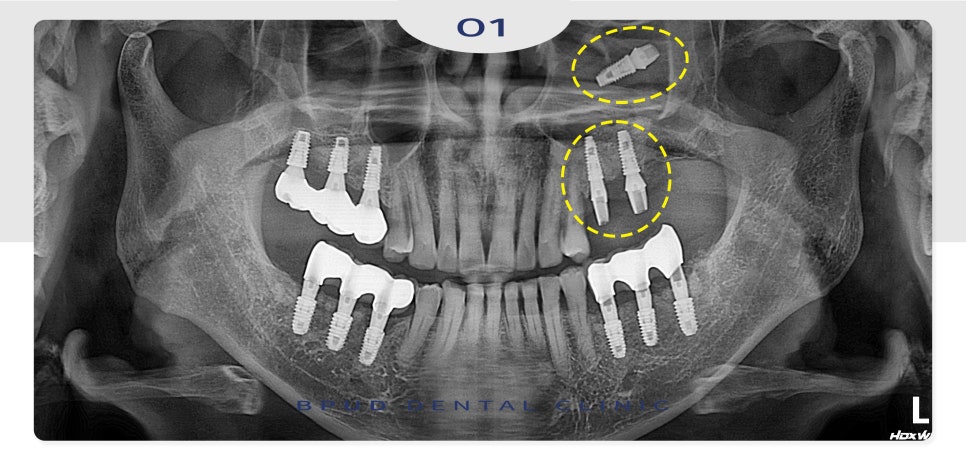

24.05.17

면밀한 진단을 위해 CT 촬영을 해보니

이미 상악동 내로 임플란트가 함입되어

있는 상태임이 명확하게 확인되었습니다.

환자분께서도 그렇게 들어간지 몰랐다고

하셨지만 코에서 냄새가 나고

콧물이 뒤로 넘어가는 증상은 있었다고 하셨는데.

상악동염도 심한 상태라

신속하게 안정적으로 제거를 완료하였습니다.